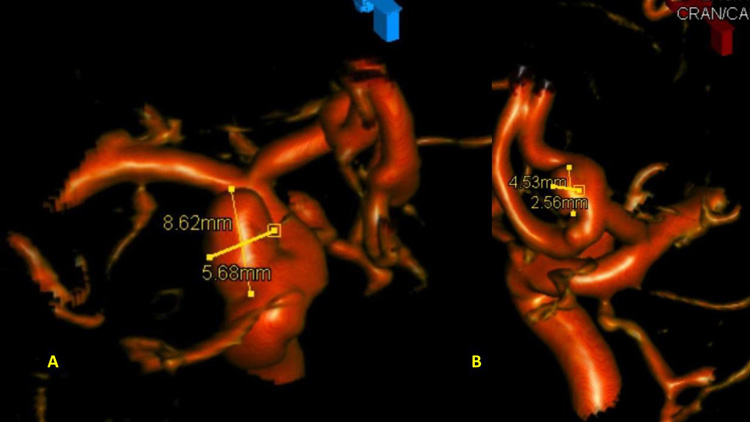

The Pattern of Hemorrhage was diffuse and generalized. On more careful analysis, however, there appeared to be focal hemorrhagic clot within the anterior inter-hemispheric fissure which raised greater suspicion for the Anterior Communicating Aneurysm as the source of hemorrhage. Although Acom Aneurysm was smaller, it’s irregular shape and eccentric “nipple” suggested potential rupture point. (Figure 3.)

After careful measurements of the parent vessels, aneurysm sac, and aneurysm neck, we decided to proceed with Primary Coil Embolization of the Acom Aneurysm first, followed by the Right ICA Aneurysm next. Despite greater suspicion in the Acom region, a significant level of uncertainty remained, and we felt it was better to secure both aneurysms if capable of being performed safely. (Figure 4.)